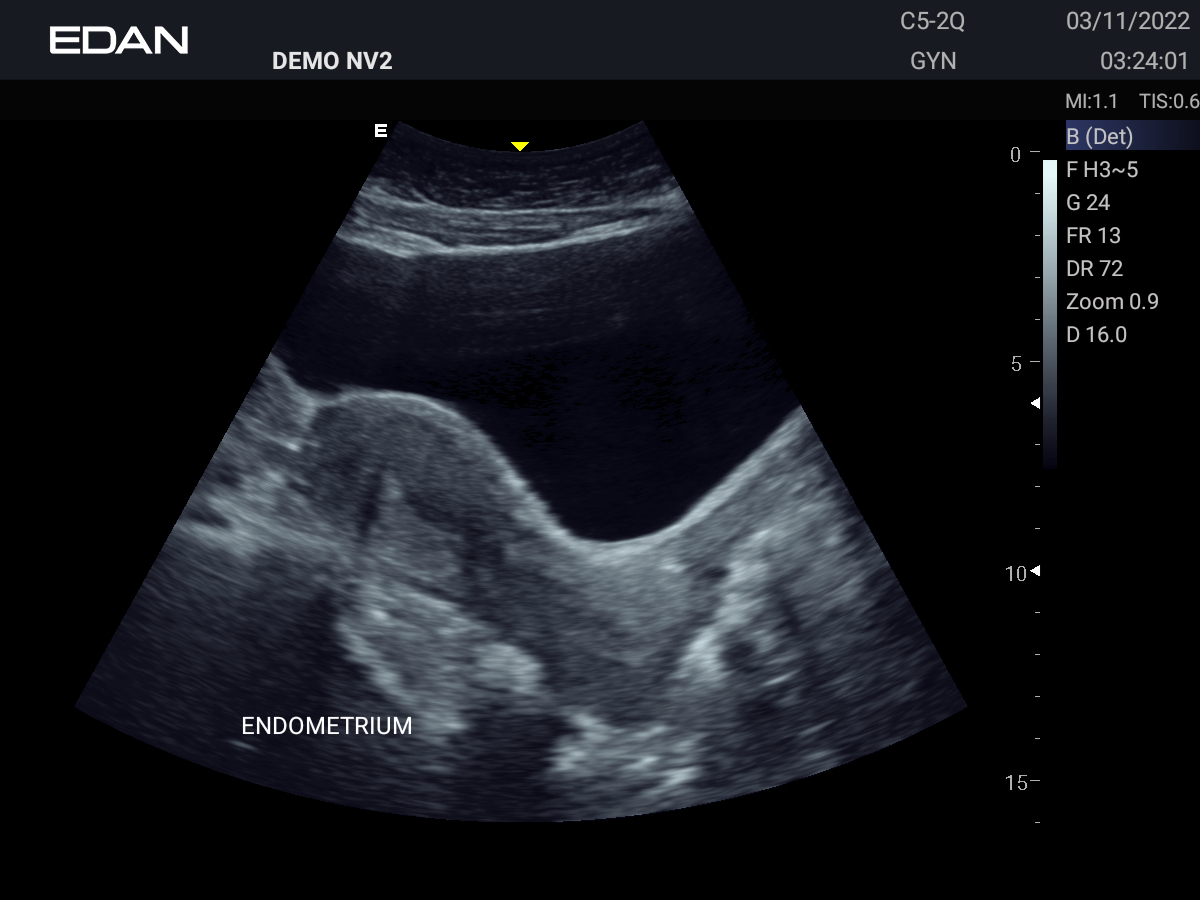

Clareza impressionante

Construído com a inovadora tecnologia Edan TAI e várias tecnologias de processamento de imagem, o Acclarix AX3 pode exibir perfeitamente a imagem de ultrassom em diferentes modos, auxiliando o ultrassonografista a fazer diagnósticos mais precisos.

Galeria de Imagens